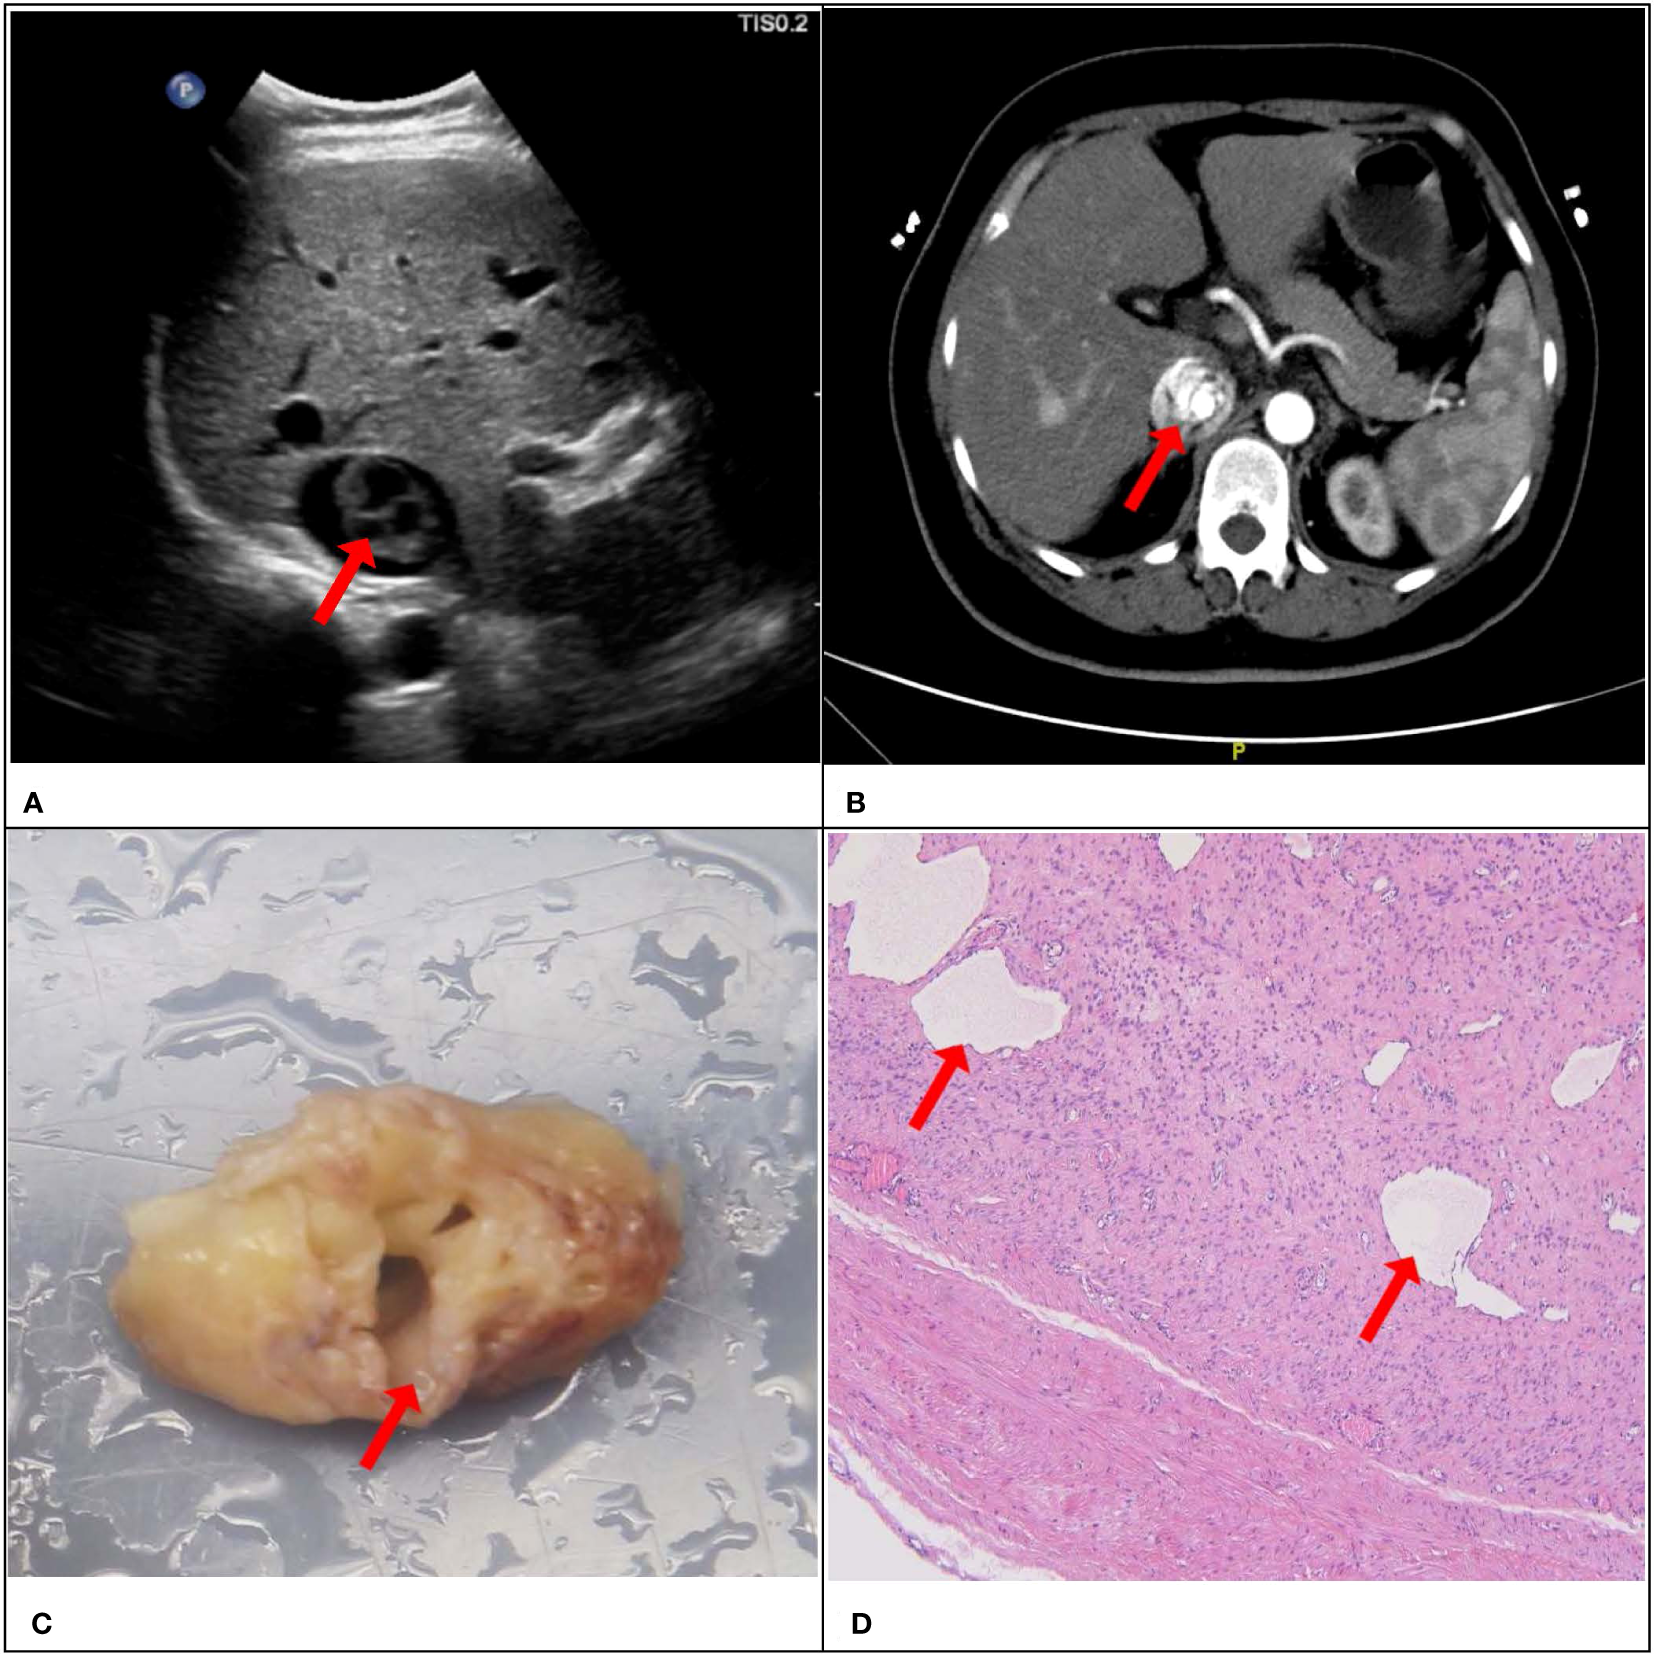

Consistency was observed between the ultrasound presentations and the pathological features in the 67 IVLs. The transverse section of the 20 tubular lesions exhibited a hollow tubular structure with a cystic appearance (Figure 4), whereas the solid cast lesions displayed a tiny lumen-like structure (Figure 5). Histopathologically, all lesions demonstrated spindle cells arranged in bundles, reduced karyokinesis, and the presence of lumens of small blood vessels.

Figure 4

A 51-year-old female patient with a surgical pathology result of IVL. Figure (A, B) showed the “sieve hole sign” under conventional ultrasound and enhanced CT respectively (red arrow). The cross section in figure (C) showed multiple circular cavities within the gross specimen lesion (red arrow), while figure (D) showed the presence of small cavity structures under the microscope (red arrow).